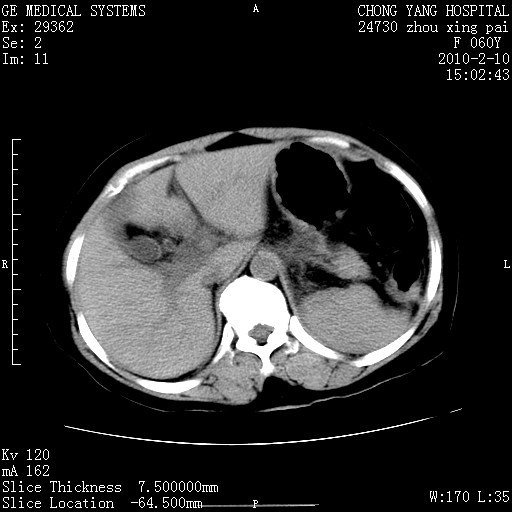

胆总管末端梗阻!结石?肿瘤?建议增强!必要时行ercp!

胆总管末端梗阻!结石?胰腺影增粗,以胰腺头部为著,胰周看见渗出影,双侧胸腔积液,(胸膜反应)考虑胰腺炎。

1)胆总管末端梗阻,不排除结石所致可能。2)胰腺炎。3)慢性胆囊炎可能。4)左侧输尿管上段扩张。5)少量腹水。6)双侧少量胸腔积液,伴两下肺部分肺萎陷。

1)胆囊炎。2)胆源性胰腺炎。3)右肾周筋膜增厚,肾旁前间隙积液。4)左侧输尿管上段扩张。5)少量腹水。6)双侧少量胸腔积液,伴两下肺部分肺膨胀不全。